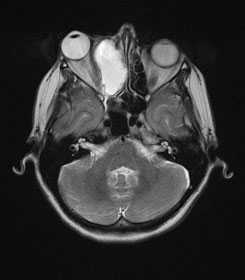

•магнитно-резонансная томография головного мозга (при наличии очаговой неврологической симптоматики)

Всех пациентов с подозрением на рак полости носа и придаточных пазух направляют на обзорную рентгенографию соответствующей области. При возможности проводят рентгенографию с использованием контрастного вещества, КТ и МРТ. При подозрении на прорастание рака околоносовых пазух в полость черепа назначают рентгенографию черепа. В некоторых случаях осуществляют диагностическую гайморотомию. Для выявления гематогенных метастазов выполняют рентгенографию грудной клетки и УЗИ брюшной полости.

В распознавании опухолей носа существенное значение имеет специальное обследование больного оториноларингологом (риноскопия и др.), офтальмологом (исследование полей и остроты зрения, глазного дна и др.) и рентгенологом (рентгенологическое исследование, томография и др.). В ряде случаев на рентгенограмме видно, в какую сторону отдавлена сохранившаяся часть костной стенки, отделяющая полость носа от глазницы, что помогает определить направление роста опухоли (из глазницы в полость носа или наоборот). Компьютерная томография (КТ) или магниторезонансная томография (МРТ) дополняет полученные данные. Прогноз при прорастании опухоли в орбиту всегда серьезный.